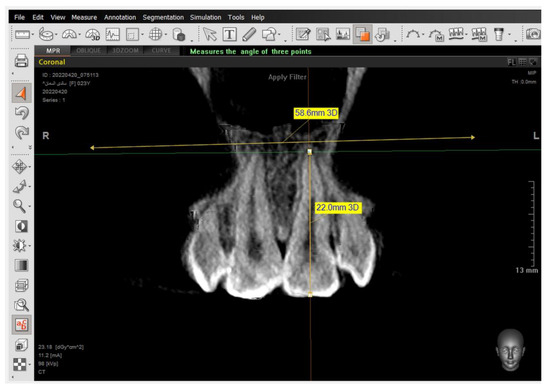

The same steps were performed for the 2nd premolars but in different directions—in the coronal window for referring buccal alveolar ridge and dehiscence and fenestrations, and in the sagittal window for determining the tooth axis.

The presence of the dehiscence and fenestrations (Figure 5), and the distance between the buccal alveolar crest perpendicular to the reference jaw plane for centrals and canines in the sagittal view were measured (Figure 6), as well as the 2nd premolars in the coronal view in maxilla and mandible (Figure 7) at T0 and T2.

Figure 7. Setting the tip of the alveolar bone crest. Then, measuring the distance between the tip of the buccal alveolar bone crest and the maxillary plane.